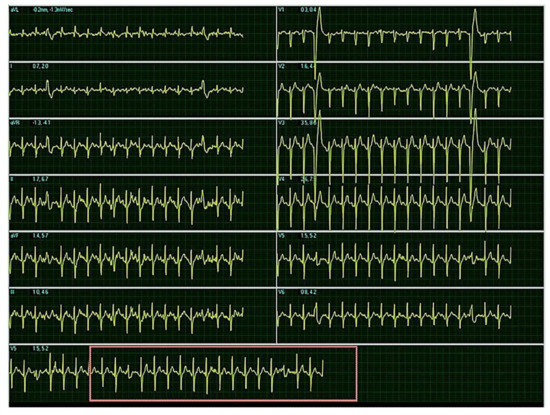

2. Case Report